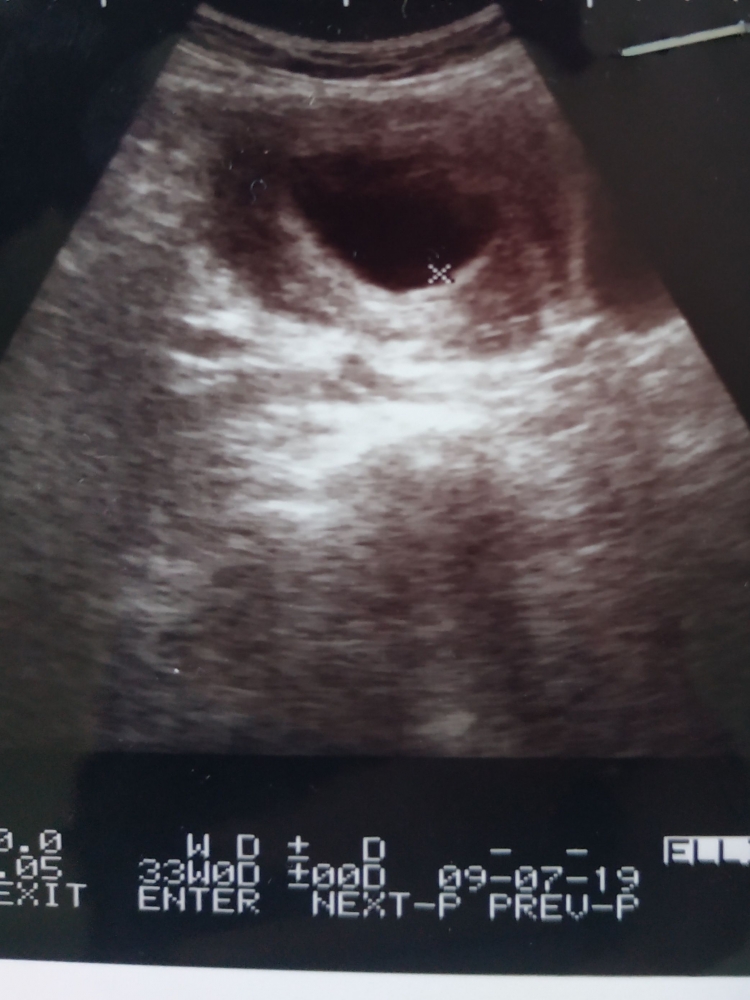

Contoh hamil 7 minggu. Usia 7 minggu kehamilan baru terlihat kantung hamil saja hamil kembar tapi satu kantong help me bund. Rasa mual dan muntah ini muncul saat kandungan berusia 1 minggu bahkan ada yang sampai 3 minggu. Ibu mengatakan saat ini sedang hamil anak pertama usia kehamilan 24 minggu dan. Bayi dalam kandungan anda juga sedang membesar dengan cepat dan kini dia sudah berukuran kira kira 10mm panjang ii sebesar saiz buah beri biru. Minggu ini menyaksikan pembentukan tali pusat bayi anda talian hayat yang menhubungkan bayi dalam kandungan anda kepada anda dan yang menyalurkan nutrien daripada anda kepadanya i. Usg usia 7 minggu baru nampak kantung kehamilan.

Membaca hasil usg ni bund usia 8 minggu detak jantung belum terlihat. Hamil 7 minggu apa yang dirasakan di perut. Contoh askeb pada ibu hamil normal 7122016 askeb bidan contoh askeb ibu hamil comment asuhan kebidanan ibu hamil normal tm ii. Kadar hormon yang berubah saat hamil menyebabkan rasa pedih pada bagian perut sehingga menimbulkan rasa mual bahkan hingga muntah. Apa yang berlaku pada minggu 7 kehamilan saya. Usia kehamilan 8w belum tampak janin.

Perkembangan bayi dalam kandungan 7 minggu perkembangan fetus bayi ibu hamil 7 minggu hamil minggu ketujuh tanda hamil usia 7 minggu kondisi keadaan ibu hamil umur kandungan minggu ke 7 bila tarikh mengandung gambar bayi janin 7 minggu tips menjaga kehamilan ibu mengandung saiz bayi usia kehamilan 7 minggu sebesar biji kacang kuda cara baca alat ujian hamil upt urine pregnancy test. Selain dua kondisi gambaran hasil usg kehamilan 5 minggu yang ditunjukan diatas beberapa ibu hamil terkadang sudah dapat terlihat adanya janin di dalam kantung kehamilan. Dari minggu ke 11 hingga ke 20 separuh perjalanan kehamilan ini bayi anda akan bertambah panjang hingga tiga kali lipat dan beratnya juga bertambah sebesar 30 kali lipat. Pusing adalah ciri awal kehamilan saat usianya 1 minggu atau hingga 3 minggu tergantung kondisi tubuh ibu. Namun perlahan tapi pasti perkembangan proporsi tubuhnya akan berlanjut pada minggu minggu berikutnya dan bayi anda akan semakin terlihat seperti manusia mungil.